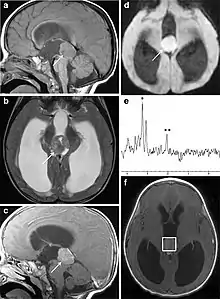

Pineoblastoma on brain imaging

Several imaging methods can be used to diagnose pineoblastoma. Initially, urgent CTs are recommended, followed by MR imaging.[13] CT will show large, multilobulated masses with heterogenous contrast enhancement and peripheral calcification of the pineal gland.[4][3] On MRI, pineoblastomas again appear as masses with heterogenous enhancement. They often appear hypo- to isointense on T1 and slightly hyperintense on T2-weighted images. Some areas of necrosis or hemorrhage may be seen as well. PET-CT has also been used in diagnosis, and shows increased uptake of fludeoxyglucose with pineoblastomas compared to other pineal masses.